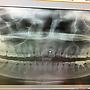

[請益] 門牙牙根斷裂後根管治療(附X光片)消失

[ teeth_salon ]30 留言, 推噓總分: +6

作者: holicadlib - 發表於 2018/06/11 21:07(8年前)

1Fholicadlib: 我並沒有怪花蓮的醫師,醫師很詳細說明,只是覺得自己06/11 21:12

2Fholicadlib: 大概什麼地方沒溝通好,很沮喪......06/11 21:12

10Fholicadlib: 謝謝yuraH醫師回覆。想請問:1.但是我根管沒在桃園診06/12 00:43

11Fholicadlib: 所做完療程,又回去請醫師做根尖切除是否對他不太尊06/12 00:43

12Fholicadlib: 重?2.我查到的資訊,根管專科預約大概都要等半個月以06/12 00:43

13Fholicadlib: 上,這段時間對牙齒而言是可等待的嗎?現在剛根管完06/12 00:43

14Fholicadlib: 所以碰到會悶痛。3.如果不回桃園診所,找根管專科跟口06/12 00:43

15Fholicadlib: 腔外科哪一個比較合適呢?06/12 00:43

16Fholicadlib: 謝謝ivanoki大。主要是後續觀察追蹤如果在花蓮做會很06/12 00:50

17Fholicadlib: 不方便,因此希望能回桃園治療。花蓮診所的醫師非常06/12 00:50

18Fholicadlib: 詳細向我說明治療情況!06/12 00:50

25Fholicadlib: 好的!謝謝yuraH醫師、balpee2大,今天打電話回去桃06/12 20:10

26Fholicadlib: 園診所了,希望後續治療順利!06/12 20:10